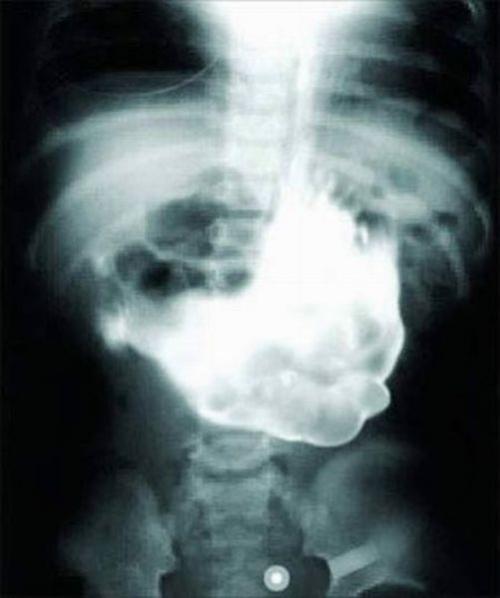

Неопознанное